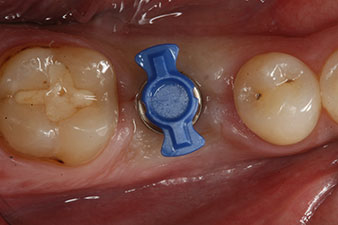

Fig. 1 : Situation clinique initiale après cicatrisation de l’alvéole où se trouvait la dent 36. La base osseuse est large et la gencive kératinisée suffisante.

Un patient de 28 ans ayant des antécédents de tabagisme important a dû se faire extraire la dent 36 à la suite d’une parodontite apicale récidivante.

Vu que les dents voisines étaient globalement intactes, la seule solution pour remplacer la dent manquante était de poser un implant.

l’ossification de l’alvéole est incomplète

Fig. 2 : Six semaines plus tard, l’ossification de l’alvéole est incomplète dans la région de la racine mésiale.

Cependant, six semaines après l’extraction on observe une ossification incomplète après la préparation du lambeau mucopériosté dans la région de l’ancienne alvéole mésiale.